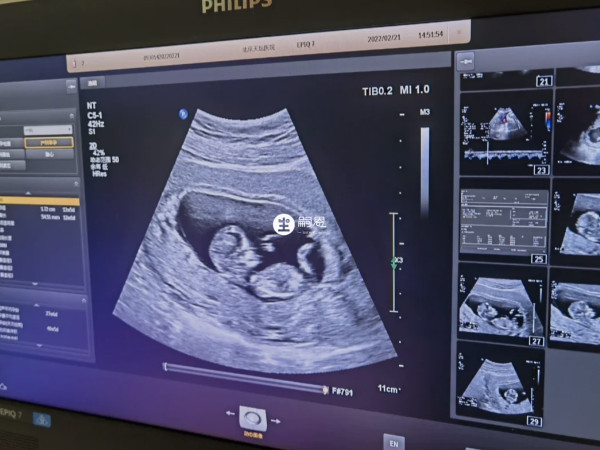

NT检查除了用于筛查唐氏综合征,部分已生孩子的宝妈还表示,nt查看生男生女准确率高达90%。孕妈们在做NT检查的时候通常会通过图像中的小尾巴来观察男女,网传如果NT图像中尾巴是上翘的话,则说明怀男孩的几率大,如果NT图像中尾巴没有上翘,呈现出平行的话,怀女孩的几率大。

如下图所示,可见胎儿双腿之间的小尾巴没有倾斜角度,整个脊柱和屁股看上去都是一条平行的线,这种图像代表是女孩的。

如下图所示,可见胎儿双腿之间的小尾巴一个很明显的陡峭往上指,屁股也微微上翘,整个后背脊柱弯成了圆弧状,这种图像就代表是男孩。

NT图像上胎儿尾巴没翘不一定就表示怀的女孩儿,也有可能怀的是男孩,但实际上这种方法并不科学,只是部分孕妈们个人总结的经验,并不能说明什么,更不能当做判断胎儿性别的依据。生男生女主要是由性染色体决定的,几率各占50%,所以不管nt图像是怎样的,怀男孩和还女孩的概率也都只有一半。

通过NT图像小尾巴是否上翘分辨宝宝性别是一个随机性事件,除了这个方法以外,通过NT报告中的数据大小、字母标志、双顶径、胎心率以及NT图像上的尾椎骨和三道杠等方法进行胎儿性别的判断,都是没有科学依据的。